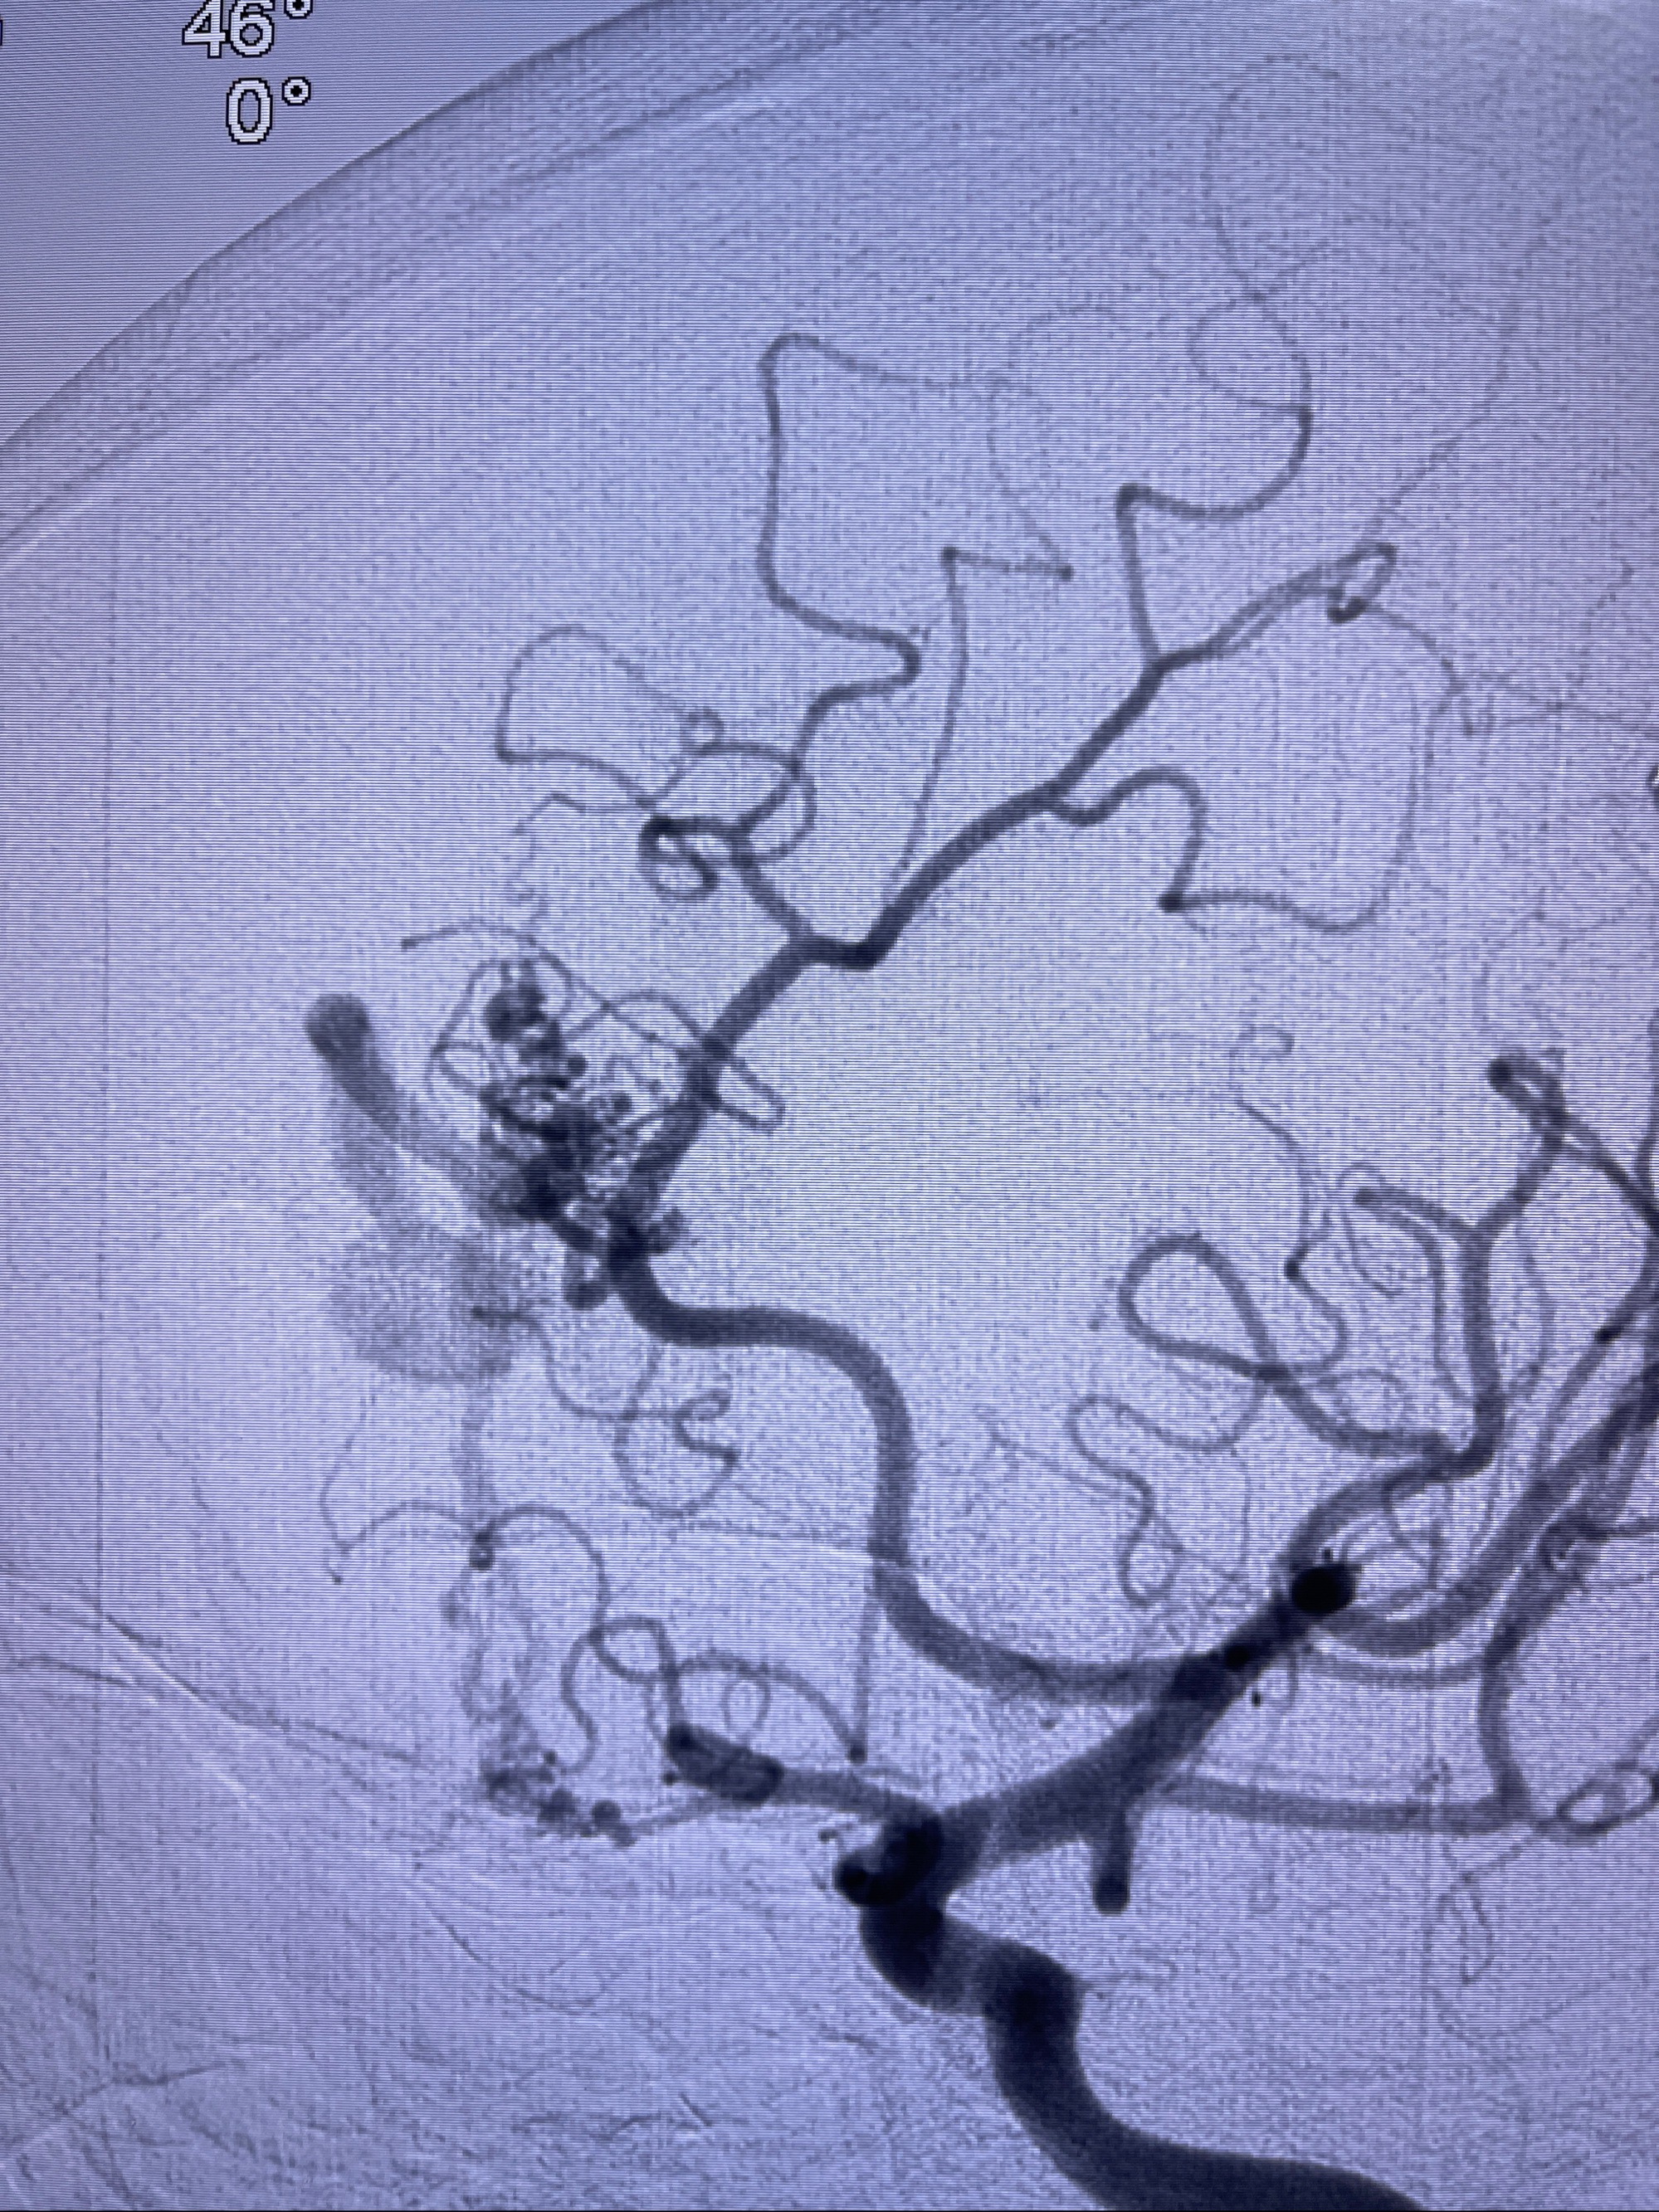

2023年8月21日]景德镇市第一人民医院脑血管造影检查,提示:主动脉弓、双侧颈总动脉、锁骨下动脉造影未见异常,左侧大脑前动脉静脉瘘。

2023-09-13全脑血管造影:前颅底硬脑膜动静脉瘘,供血动脉为双侧胼周动脉、眼动脉脑膜支,静脉向上矢状窦方向引流